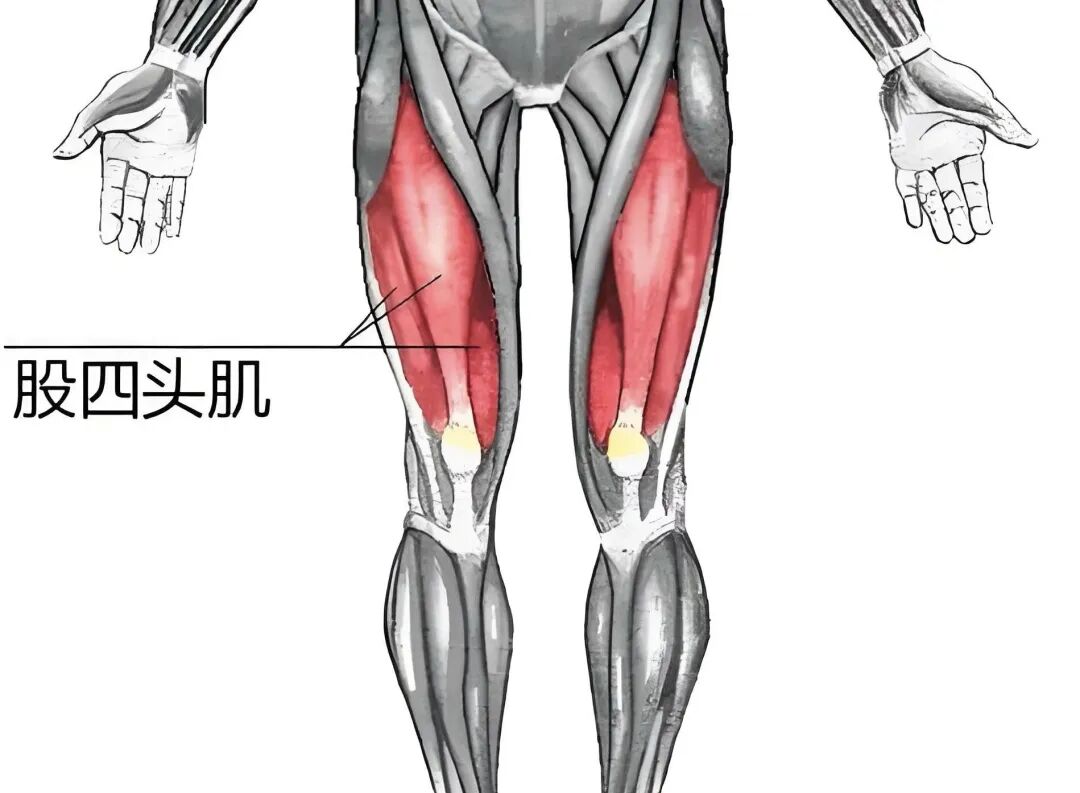

一块影响膝盖健康的肌肉

存在着诸多致使膝盖受伤的因素,大多数人却忽略了“肌肉力量不足”这一因素。

据北京清华长庚医院骨科与运动医学中心主任医师陈连旭介绍yy漫画画免费读漫画下拉式在线观看,在膝关节上方存在着一种被称作“股四头肌”的肌肉,这种肌肉,对于膝关节的稳定性而言,十分重要,对于缓冲关节压力而言,十分重要,对于保护软骨来说,同样十分重要。

即是说,这块肌肉越发强壮,身体的每个动作给膝盖施加的压力就会越小,膝关节的使用期限也会得以延长。当股四头肌力量欠缺时,膝盖骨易于内偏,致使摩擦与疼痛加剧。